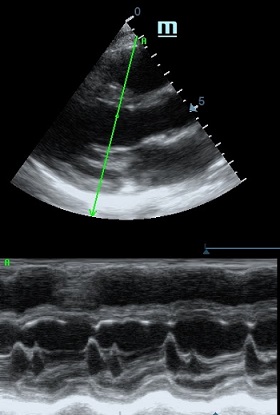

Оценка сокращения сегментов левого желудочка на глаз постепенно уходит в прошлое. Если в приборе нет функции радиального или лонгитудинального стрейна, на помощь опять может прийти Free Xros. Утолщение более 5 мм в систолу – нормальное сокращение, 2-5 мм гипокинез, истончение в систолу – дискинез.